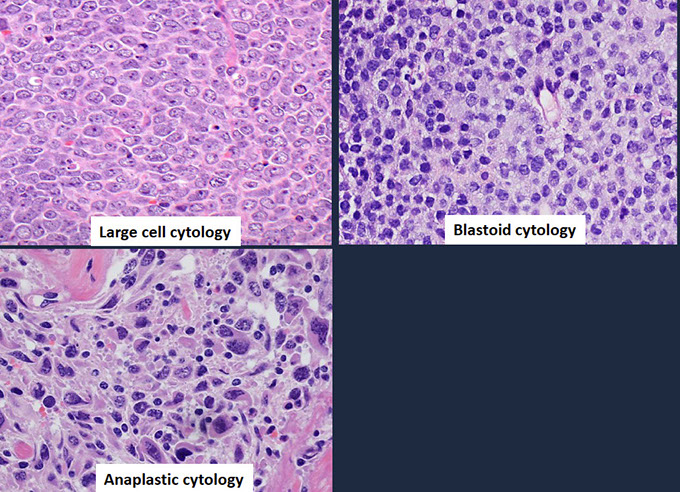

High-grade B-cell lymphoma

- High-grade B-cell lymphoma with MYC and BCL2 and/or BCL6 rearrangements

- High-grade B-cell lymphoma, NOS